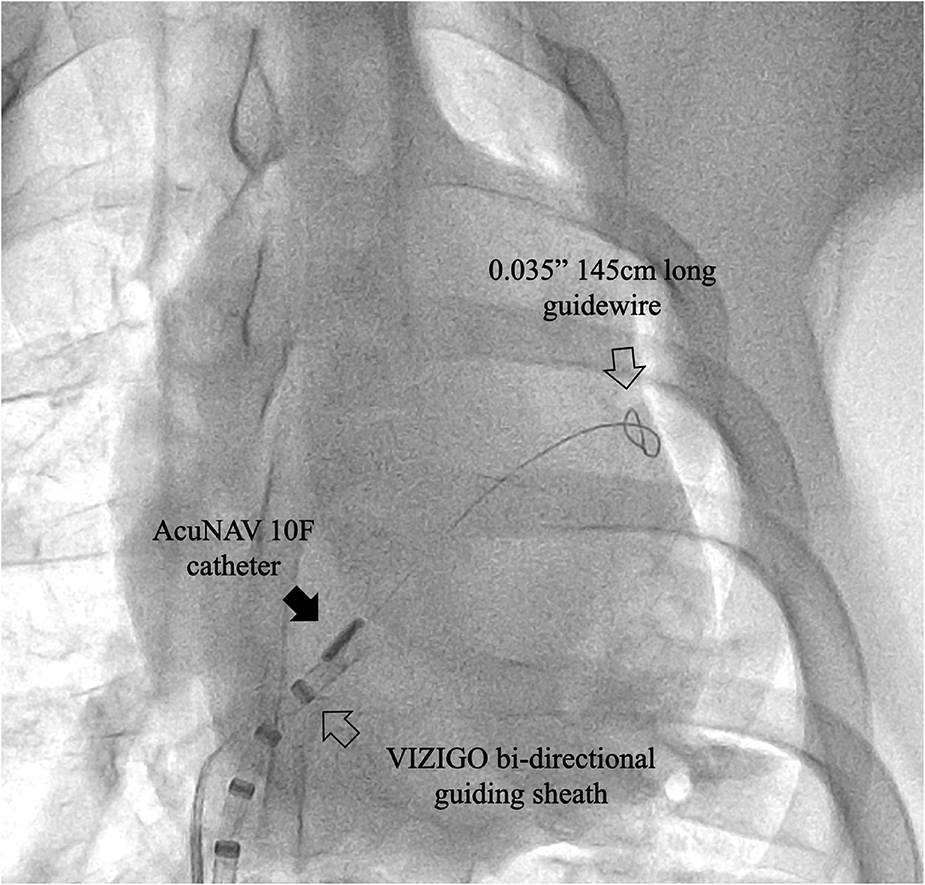

In the sheath-less trans-septal porcine model, two operators attempted to advance a commercially available ICE catheter (AcuNAV 10F) into the left atrium along a guidewire after multiple attempts. The puncture site was enlarged using an 11.5F steerable bi-directional guiding sheath (VIZIGO, Johnson and Johnson MedTech) before, and no balloon was used. It should be note that the inner diameter of the VIZIGO sheath is 8.5F and not suitable for the AcuNAV 10F catheter. For current ICE catheters, a trans-septal sheath with an inner diameter of at least 10F is required. The entire process took 33 min, including a fluoroscopy time of 18 min. Both of these durations are notably extended, considering that neither operator had prior experience with this off-label procedure (Figure 5).

Figure 5

Case 0, x-ray image showing the ICE catheter positioned within the septum area. Note that the tip of the AcuNAV catheter is aligned parallel to the VIZIGO sheath and faces the site where the long guidewire passes through the atrial septum. The sheath and guidewire serve as markers in this process.